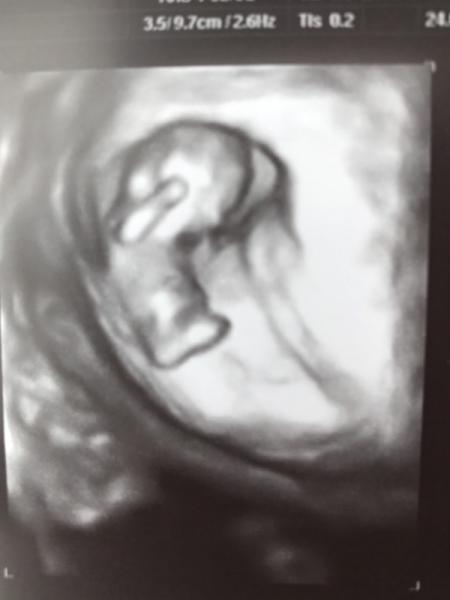

Ich will mich ja auch nicht verrückt machen, aber mich verwundert es! Meine Blase war bei der Untersuchung auch nicht ganz leer, vielleicht lag es daran?! Meine Freundin sagte, es würde für sie so aussehen, als wenn das Kind auf dem Rücken liegt, vielleicht erkennt man daher so wenig?! Meine Freundin sagt, sie würde Ansätze von Beinen und Armen sehen. Ich sende mal ein Bild, vielleicht könnt ihr dann ja mal beurteilen, ob und wie es für euch aussieht. Danke !!

Bild zu Foto bewerten, 9+ keine arme und Beine zu erkennen?! - Schwanger - wer noch? Rund um die Schwangerschaft